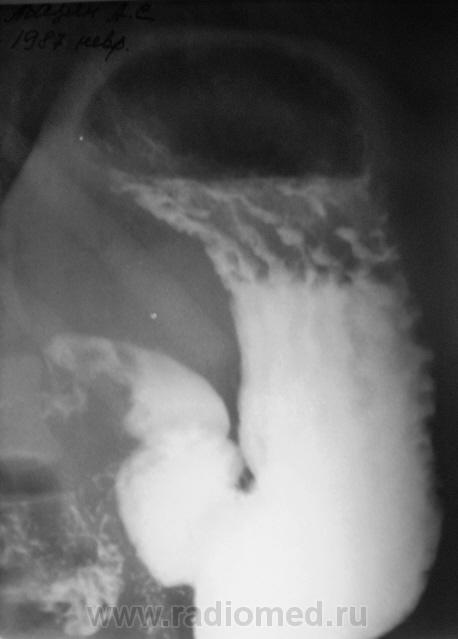

Вообще довольно часто встречающаяся ситуация с военкоматом, когда эндоскосписты, что-то нашли, а "рентген" не нашел. Но в данном случае наоборот - эндоскописты кроме "гастритика" ничего не нашли, рентгенологи дали заключение о наличии язвенной болезни 12-ти перстной кишки. Что делать терапевту, который будет писать акт, что делать эксперту, который будет выносить решение?

Принесли вот такие сгимки, спрашивают мнение.

"Язва" луковицы есть.....и на "рельефе" и на "конутре" "ниша" просматривается. Может у кого то будет другое мнение. послушаем.

На всей серии снимков формально - ниша в луковице. Однако на всех же снимках она хорошо заполнена, нет раздражения - главного косвенного признака... Возможно это в гипотонии? А в заключение - рубцовая деформация...

Релаксация не проводилась.